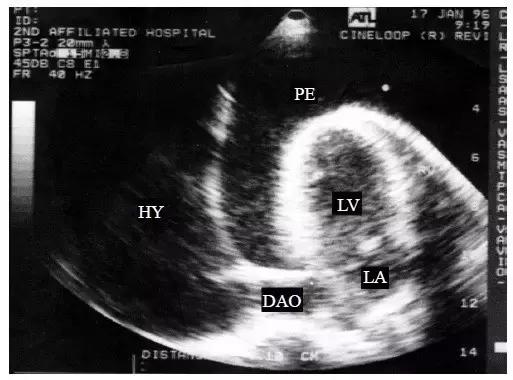

【大量心包积液】

1.整个心脏被无回声区所包绕,心尖及左心室后壁心包腔内暗区最宽(图3)。

图3 大量心包积液的二维超声心动图表现

整个心脏被无回声区所包绕,心尖及左心室后壁心包腔内暗区最宽

2.大量积液无心包粘连时,悬吊在大血管下的心脏可在液体内自由摆动,称“摆动征”,即收缩后期向前运动,舒张期向后运动,摆动的幅度与液体的黏稠度密切相关。右心室前壁活动幅度增强,呈波浪式运动,左心室后壁幅度降低。